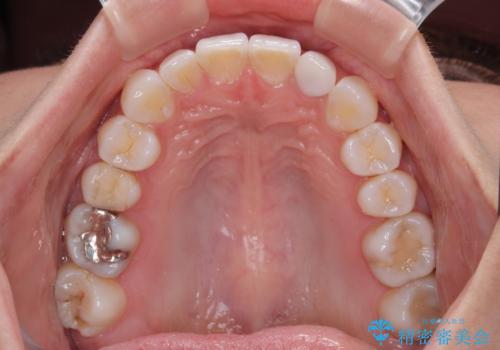

【モニター】前歯のデコボコと小さい前歯 インビザライン矯正とオールセラミッククラウン補綴治療

- 前歯の歯並びと生えてきたときから小さい前歯を気にして来院された患者様です。

上下前歯の歯列不正はインビザラインにより整え、その後に、矮小歯の前歯をオーダーメイドタイプのオールセラミッククラウンにて補綴治療することとしました。

セラミッククラウンにて大きさを変更することを前提に矯正治療を開始したため、大変満足のいく仕上がりとなりました。